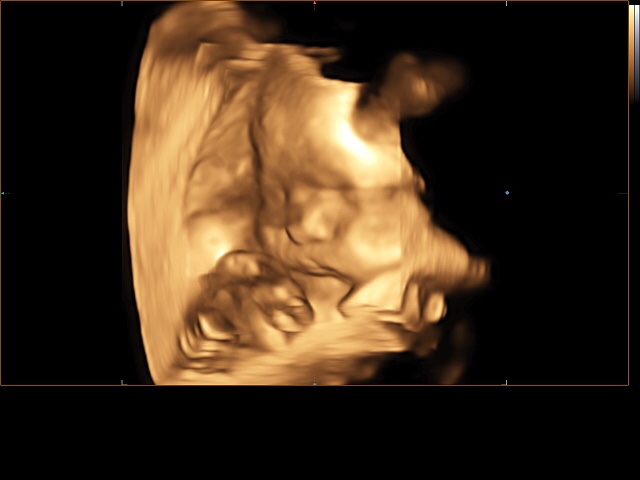

А вот и наш третий скрининг)))) все в норме! По весу 1800. Врач сказала хороший щекастый мальчик с большой морковкой 😂😂😂😂

Делали 4д с записью на диск видио и фото